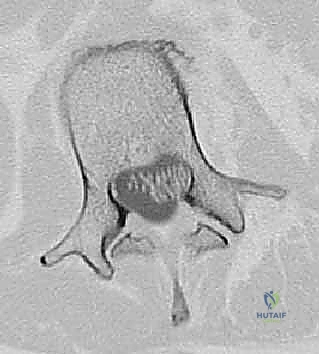

عملية دمج الفقرات (Spinal Fusion) هي إجراء جراحي يهدف إلى ربط فقرتين أو أكثر بشكل دائم، مما يزيل الحركة غير الطبيعية والمؤلمة بينهما، ويعيد الاستقرار الميكانيكي إلى العمود الفقري. في حالتنا هذه، يتم التركيز بشكل خاص على المنطقة الصدرية القطنية (Thoracolumbar Junction)، وهي المنطقة الانتقالية الحرجة التي تربط الجزء العلوي من الظهر (القفص الصدري الصلب) بالجزء السفلي (المنطقة القطنية المتحركة). يتم التثبيت باستخدام أدوات طبية معدنية متطورة (Instrumentation) مثل المسامير السويقية (Pedicle Screws) والقضبان المصنوعة من التيتانيوم.

السويقات الفقارية (Pedicles): دعامة التثبيت الأساسية والمحورية

2. السويقات القطنية (L1-L5):

* الحجم والشكل: أوسع بكثير وأكثر قوة وصلابة من السويقات الصدرية، مما يجعلها مثالية لتثبيت المسامير الكبيرة. يميل العرض إلى الازدياد كلما اتجهنا لأسفل (الفقرة L5 تمتلك أوسع سويقات).

* التصوير المقطعي المحوسب (CT Scan): يوفر صوراً ثلاثية الأبعاد للعظام، وهو ضروري جداً للتخطيط الجراحي الدقيق وتحديد أحجام المسامير المناسبة لكل سويقة فقارية.